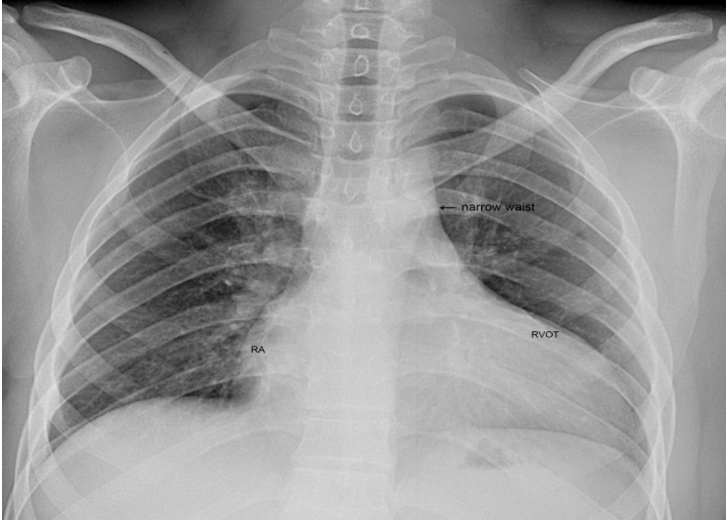

A 28-year old male presented with cyanosis and auscultation revealed a ‘sail sound’ ( loud tricuspid component of first heart sound due to increased tension developed by the large anterior leaflet as it reaches the limits of its systolic excursion- an important sign of anterior leaflet mobility), a ‘cadence’ quality of quadruple rhythm due to wide splitting of first and second sounds ( due to complete right bundle branch block), atrial and ventricular filling sounds (summation of these sounds due to prolonged PR interval). ECG revealed the features of Ebstein’s anomaly as shown in Figures 11 and 12. X-ray chest revealed the Ebstein’s configuration as shown in Figure 13. 2D echocardiography revealed a ‘sail-like’anterior tricuspid leaflet forming a ‘muscular curtain’ in between the inflow and trabecular parts of the right ventricle as an ‘imperforate membrane’ with a ‘pinhole’communication, associated with a muscular VSD (ventricular septal defect) in the proximal, atrialized compartment of right ventricle suggesting an ‘atretic” (‘imperforate’) Ebstein’s anomaly as shown in Figures 14 to 27.

Ebstein’s original case was an example of obstruction at the tricuspid orifice by a membrane dividing the right ventricle into two halves as shown in Figure 16 of a 28-year old cyanotic male with ECG and X-ray characteristics as in Figure 11 to 13. suggesting an advanced spectrum of Ebstein’s malformation , necessitating RV exclusion techniques such as Starnes’ procedure. The florid case of Ebstein’s anomaly with the insertion of leaflet tissue along with ventricular walls as a ‘blanket’ as in Figures 28 and 29 in a 30-year old cyanotic male may go for an initial palliation with bidirectional Glenn shunt (cavopulmonary anastomosis). The other variants of moderate degree of leaflet tethering with varying degrees of regurgitation, but an intact basal leaflet attachments with atrioventricular junction as in Cases 1 and 2 may need a definite repair. In Ebstein’s mitral valve as in Figure 32 in a 10-year old boy, the downward displacement of functional annulus > 0.8 cm/m2 is not particularly striking and tends to affect the septal leaflet (anterior mitral leaflet) alone. The valve is thickened and mildly regurgitant due to rheumatic involvement rather than an anatomic cause.

Ebstein’s anomaly is a rare congenital heart defect occurring in 1 in 20,000 live births in general population. [88] and in neonatal Ebstein’s anomaly, the cardiac silhouette may fill the entire chest (“wall to wall” heart) in chest X-rays [89]. The spectrum of malformation in Ebstein’s anomaly may range from only minimal displacement of the septal and posterior leaflets to an imperforate membrane or a muscular shelf between the inlet and trabecular zones of the right ventricle were documented by echocardiography and various treatment options were described in this spectrum.